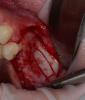

CSS Опубликовано 26 декабря, 2012 Автор Поделиться Опубликовано 26 декабря, 2012 Аккуратненько! имплантаты можно было бы побольше углубить, учитывая будущую резорбцию на биогоризонте.Спасибо!!! Относительно углубления, лично по моему взгляду, винт надо останавливать на 0,5 до гребня, т.к. Вроде бы к лазер-локу должна липнуть мягкая ткань. При заглублении заметил ремоделировку до 1-ГО, а иногда и до 2-ГО витка. При установке выше гребня, по моим наблюдениям, ее, ремоделировки, не происходит. Чисто суб'ективное мнение!!! На дентиуме, углубляюсь!!!;-)))) 3 Ссылка на комментарий

Mane Опубликовано 26 декабря, 2012 Поделиться Опубликовано 26 декабря, 2012 по вашему кейсы - импланты углубил бытакое впечатление что в области 25 не хватает графтаокно сделал бы меньше (есть же даск). ваш кусок может секвестрироватьсянужно стандартизировать фотопротокол а так все норм. спасибо за кейсработаю алло почти 2 годавсе нравится и ничего там не нагнаивается - для доктора шу Ссылка на комментарий

CSS Опубликовано 26 декабря, 2012 Автор Поделиться Опубликовано 26 декабря, 2012 по вашему кейсы - импланты углубил бытакое впечатление что в области 25 не хватает графтаокно сделал бы меньше (есть же даск). ваш кусок может секвестрироватьсянужно стандартизировать фотопротокол а так все норм. спасибо за кейсработаю алло почти 2 годавсе нравится и ничего там не нагнаивается - для доктора шу Спасибо за комментарий, но окно намеренно делалось таким, ввиду сложной анатомии в зоне 26 и 27. У меня есть Даск, и очень прикольный набор, но лично по мне не всегда применим, ввиду длинной ножки бора, об этом мы еще пополимеризуем на конгрессе в Краснодаре!!!!!! ;-)))) В зоне 25 все ок!!! Просто этот граф не всегда контрастен. А деминерализованный алло вообще не виден после операции, и бывало ощущение, что винты в воздухе, но контрольное кт, развеяло сомнения!!! ;-)))Относительно углубления, если б это был Дентиум, то углубил бы на 0,5, но тут Горизонт, о своих наблюдениях уже писал выше!!!Насчет фотопротокола, ну не всем так везет, иметь штатных профессиональных фотографов, так что не обессутьте!!! ;-))) А как у Вас с аллоблоками??? Каков протокол??? Вымачиваете??? Какую толщину ламината используете??? Ссылка на комментарий